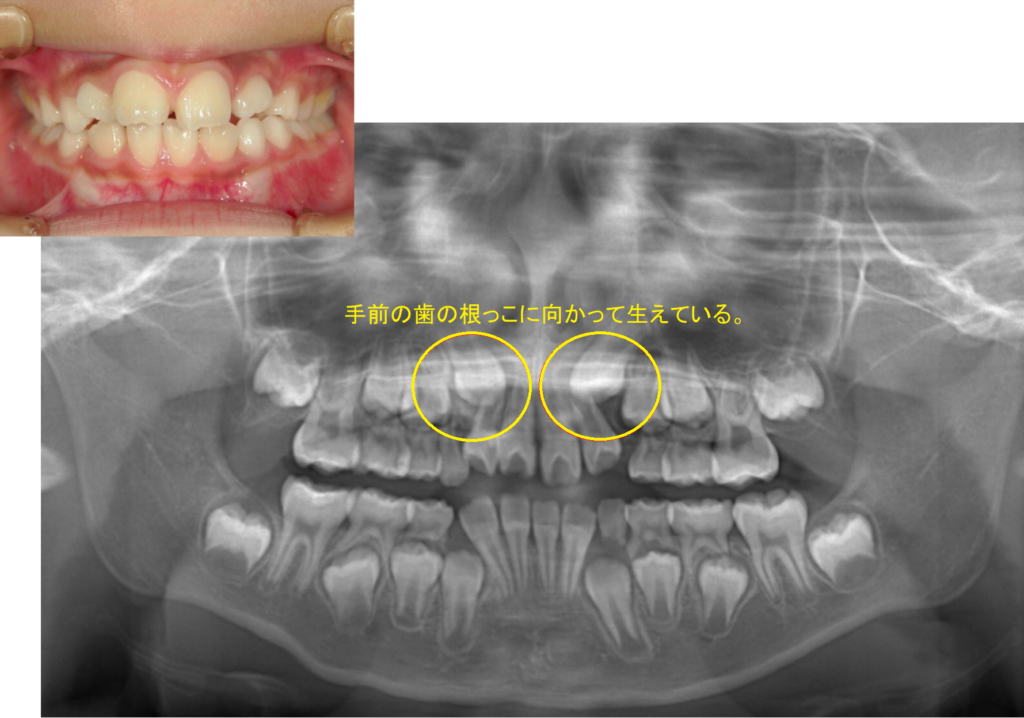

そんな日々の診療の中で、「意外と多いな、、、」と思うのが埋伏犬歯(まいふくけんし)です。

埋伏犬歯(まいふくけんし)とは

上顎の前歯から3番目である犬歯が正常に生えてこないことで、

隣の前歯の歯の根っこが無くなってしまったり、抜けてしまったりするケースです。

レントゲンでは後に生える永久歯を確認を確認することができますので、

犬歯が怪しい角度を示しているは、治療適齢期に早期治療を心がけています。